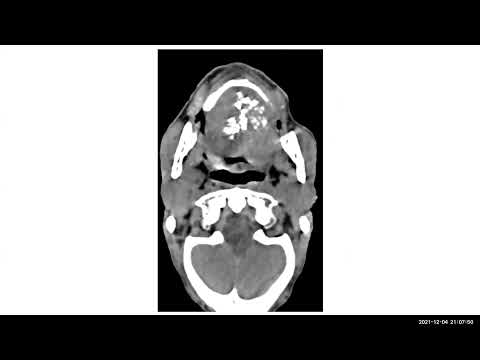

TEAM FRCR 2B Viva Practice Session (CNS Module). 8th Jan, 2022

Radiology Viva Cases # 181-187 | Brain Exam Cases Part -3 #medical #radiology #ultrasound #doppler